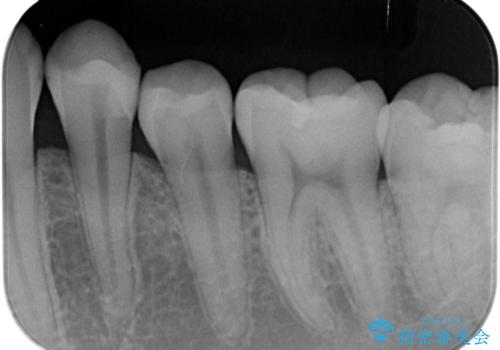

- 矯正前の患者様です。検査により虫歯がありましたのでe-maxインレー治療を行いました。

- e-maxインレー 7.7万×2費用は治療当時の料金となります

虫歯がある状態で矯正を始めてしまうと矯正治療中に虫歯が悪化してしまう可能性があります。